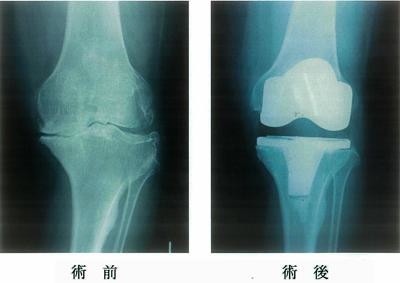

第44回 午前

74歳の女性。5年前から左膝痛が出現し、徐々に増悪して歩行が困難となったため左膝の手術を受けた。術前と術後のエックス線写真を示す。術前の所見で認められるのはどれか。2つ選べ。

1

骨棘形成

2

骨融解像

3

外反膝変形

4

特発性骨壊死

5

関節裂隙の狭小化